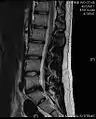

МРТ поперекового міжхребцевого диска між четвертим і п'ятим хребцями.

Приклад міжхребцевого диска L5-S1 у поперековому відділі хребта.